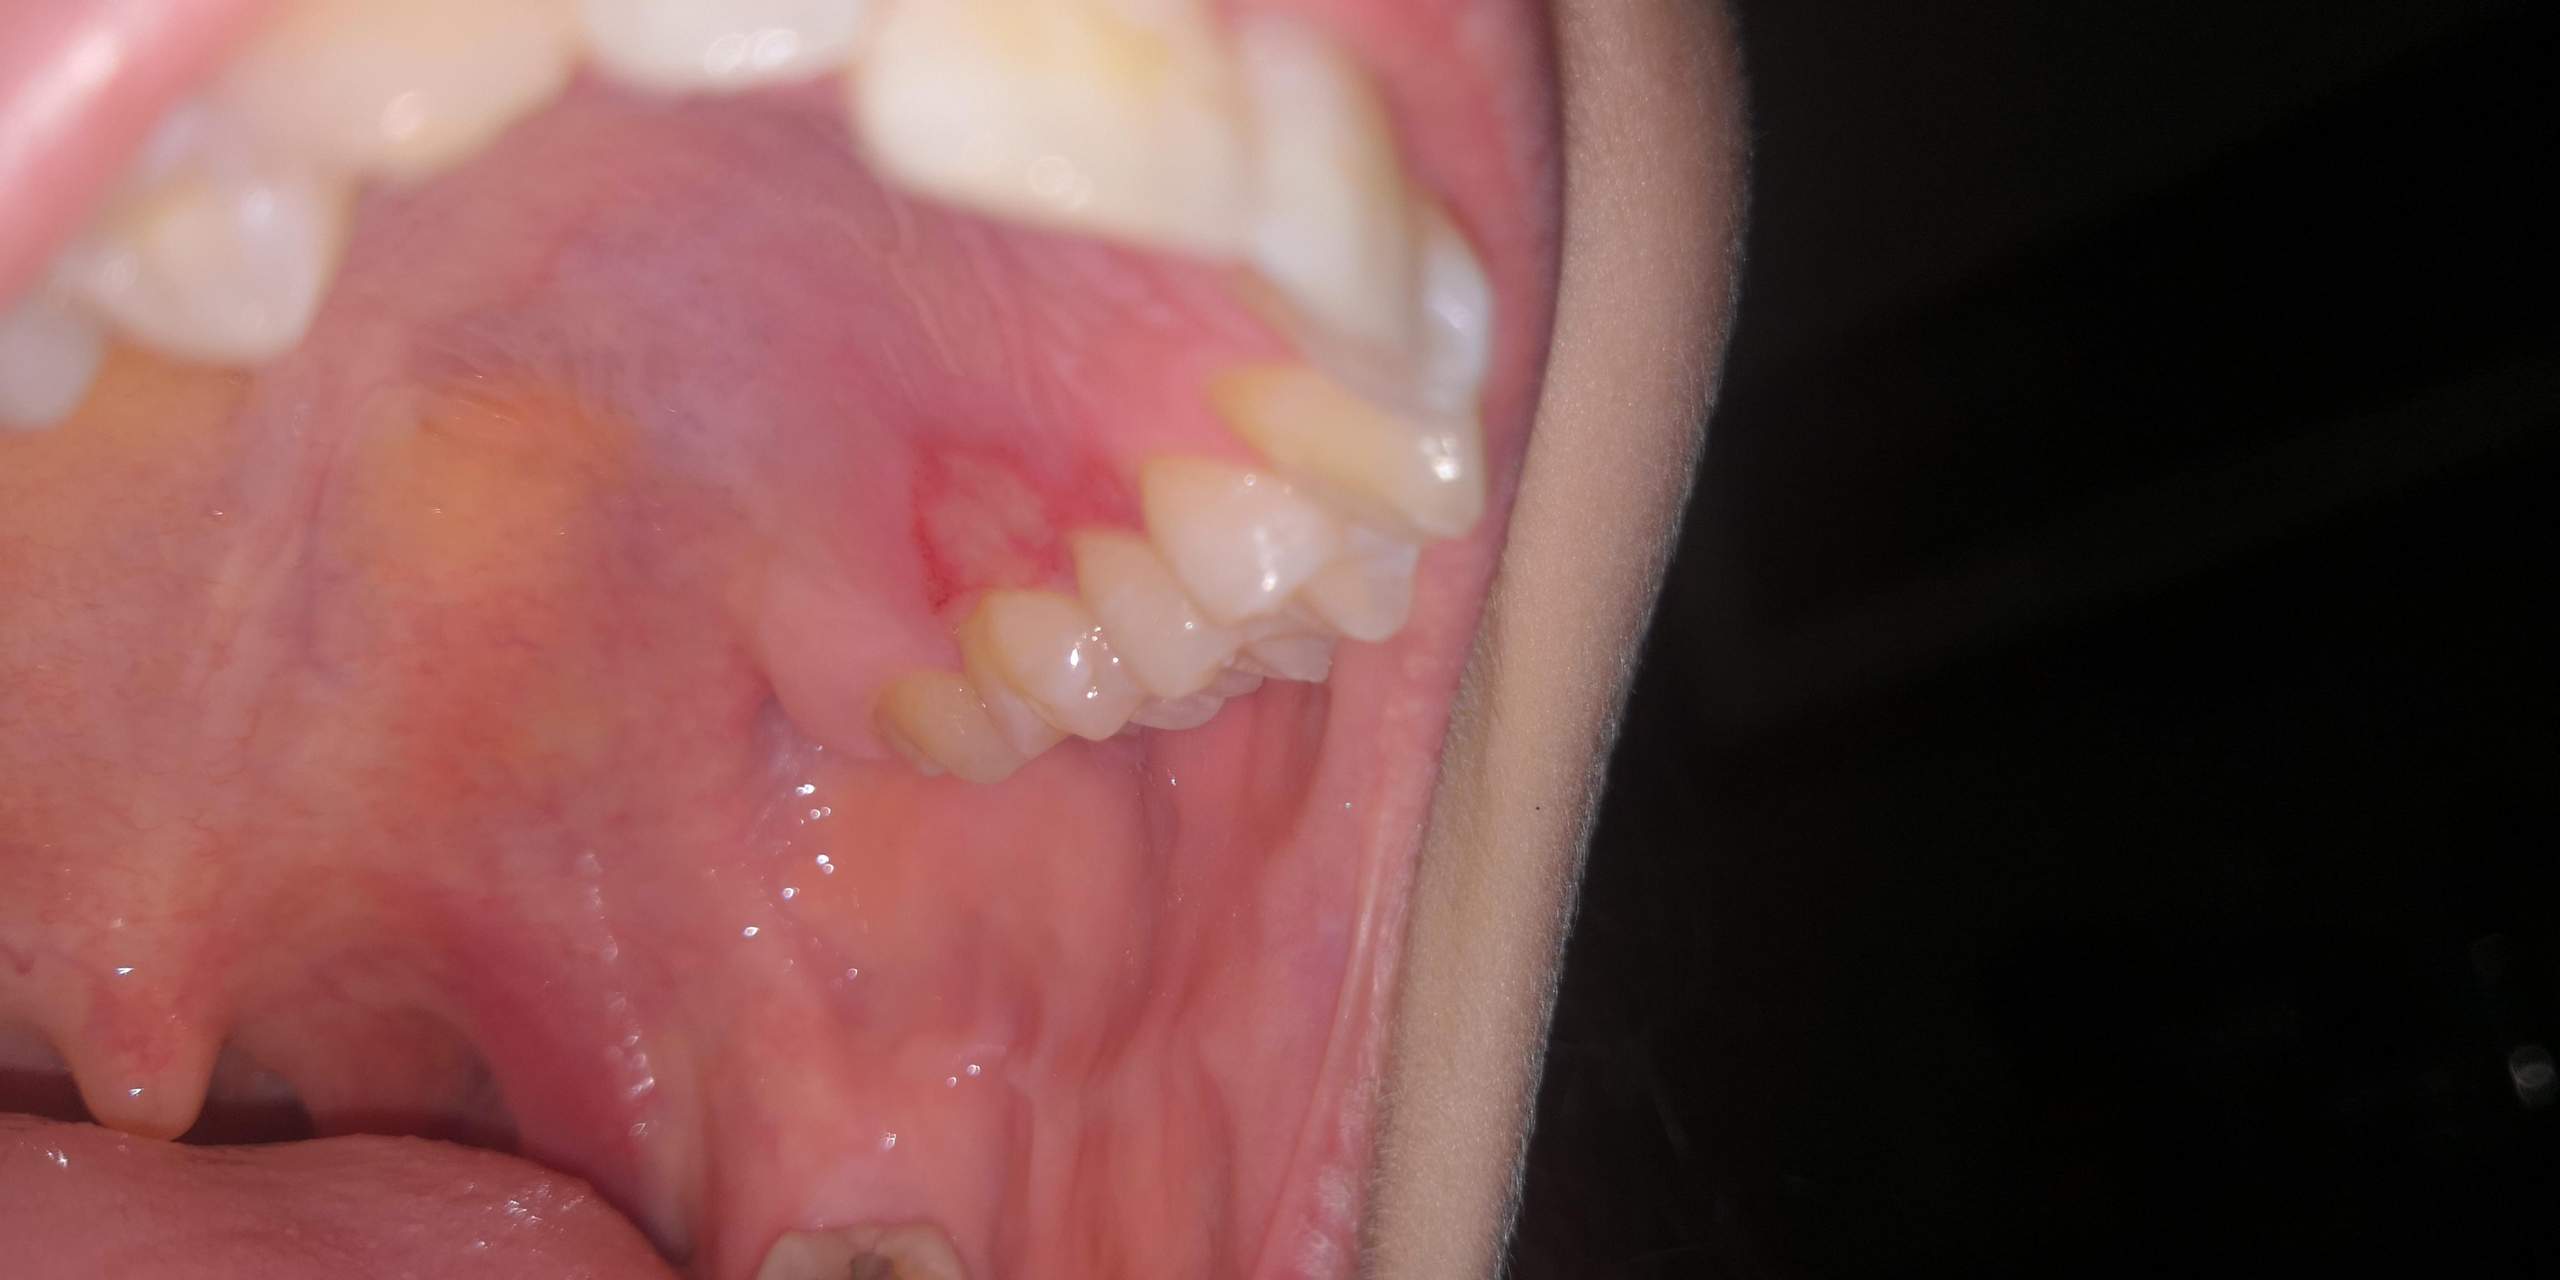

durch allgemeines Unwohlsein. Je nach Auslöser können weitere Beschwerden wie eine Rötung oder Schmerzen hinzukommen. Es entstehen zwischen Zahn und Zahnfleisch tiefe Taschen , d. Mundgeruch mit diesen 17 Tipps schnell loswerden! Was ist eine .Wer hat ein erhöhtes Risiko? So sieht gesundes Zahnfleisch aus. Wenn das Zahnfleisch geschwollen ist, kann dies folgende Gründe haben: falsche Mundhygiene. Ein erhöhtes Risiko für weitere Entzündungen bleibt jedoch. Mögliche Ursachen für eine ZahnfleischentzündungAuch ohne eine Behandlung kann eine Zahnfleischentzündung wieder zurückgehen. Die Interdentalraumreinigung ist deshalb unumgänglich zur Vorbeugung und Behandlung von Zahnfleischentzündungen.Kommt es zu einer Zahnfleischentzündung, einer sog. Test Zahnfleischentzündung.Diese „normale“ Zahnfleischentzündung befindet sich meist versteckt zwischen den Backenzähnen. Häufigstes Symptom: Zahnfleischbluten.Um die Zahnfleischentzündung einzudämmen kann eine in der Apotheke erhältliche antibakterielle Mundspülung verwendet werden. Während die meisten an schwächeren Formen leiden, haben rund 11 Millionen von uns eine . Symptome und erste Anzeichen sind neben dem Zahnfleischbluten, ein empfindliches Zahnfleisch beim Zähneputzen. Unbehandelt führt sie zu weiteren Komplikationen, wie zum Beispiel der Parodontitis.Ein erstes und häufiges Symptom einer Zahnfleischentzündung ist, dass das Zahnfleisch bei Berührung oder beim Zähneputzen anfängt zu bluten. Sie ist eine frühe, milde Form der Zahnfleischerkrankung.Dadurch, dass das Zahnfleisch nicht mehr an der Zahnoberfläche haftet, weitet sich die Zahnfleischtasche (die Lücke zwischen Zahn und Zahnfleisch wird . Dabei werden durch eine professionelle Reinigung die Zahnoberflächen, die Wurzeloberflächen und die Zahntaschen von Bakterien befreit.Entzündungen am Zahnfleisch äußern sich allgemein durch Schmerzen beim Kauen, Blutungen, gerötete Stellen im Mund bzw. Die Gingivitis äußert sich in Form von Rötung, . Schöne und gesunde Zähne, eine gesunde Mundflora und eine gute gesundheitliche Verfassung sind nur mit gesundem Zahnfleisch möglich. Die Risikofaktoren für Zahnfleischentzündungen ähneln den . Je tiefer sie sind, desto weiter . Sie reizen das Zahnfleisch und können zu dessen .Grundsätzlich unterscheidet man zwischen der akuten-, chronischen-, akuten nekrotisierende und ulzeröse sowie hormonelle und desquamative Zahnfleischentzündung. Hormonelle Veränderungen. › Inhalt aufklappen. In jedem Fall sollte bei andauernden .Oft bemerkt man Zahnfleischentzündungen gar nicht, so häufig kommen sie vor und so unauffällig ist meistens der Verlauf.

Durch die Entzündung bildet sich ein Raum zwischen Zahn und Zahnfleisch, der die Ansiedlung von Bakterien noch begünstigt. Die Zahn- und Mundgesundheit hat einen großen Einfluss auf das körperliche und seelische Wohlbefinden. Weil Zahngranulome meistens an entzündeten Zähnen auftreten, ist eine . Hinweis: In diesem Artikel lesen Sie mehr über typische Symptome einer Zahnfleischentzündung. Die an der Entstehung von . Die akute Gingivitis Diese Form der Zahnfleischentzündung lässt sich in der Regel leicht behandeln und liegt meistens in der Ursache von . Wie wirkt die Zahnfleischentzündung .Je länger die Entzündung anhält, desto schlimmer werden die Symptome. Symptome, Verlauf und Folgen einer Gingivitis.Eine Zahnfleischentzündung macht sich durch gerötetes oder geschwollenes Zahnfleisch und Zahnfleischbluten bemerkbar.

In diesen Taschen vermehren sich Bakterien, die zu Zahnfleischentzündungen sowie zu Karies Karies Bei Karies handelt es sich um zerstörte Bereiche im Zahn infolge eines Vorgangs, bei dem sich allmählich die harte Zahnoberfläche (Zahnschmelz) auflöst, bis .Zu einer Zahnfleischentzündung kommt es am häufigsten bei unzureichender Mundhygiene mit Zahnbürste und Zahnseide. Erkrankte Zähne.Im Normalfall entsteht die Zahnfleischentzündung so: Wenn Zähne und Zahnzwischenräume nicht regelmässig und gründlich gereinigt werden, bildet sich Zahnbelag – vor allem am Zahnfleischsaum. Folgende Symptome können auf Zahnfleischtaschen hindeuten: geschwollenes, empfindliches Zahnfleisch.Zahnfleischentzündung / Gingivitis. Sie wird durch sehr aggressive Bakterien verursacht und verläuft deshalb besonders dramatisch und schnell. Wird aus diesem weichen Belag Zahnstein, ist es viel einfacher, dass eine Tasche ausgebildet wird, da der Zahnstein die Weichteile vom Zahn abhält. Was ist eine Zahnfleischentzündung? Was tun bei . Schmerzendes Zahnfleisch als Symptom. Entzündungen (Gingivitis oder Parodontitis) Abszesse.Zahnfleischentzündung – das sind die typischen Schmerzen! Leiden Sie an einer Zahnfleischentzündung. Die Entzündung dringt durch die verschiedenen Schichten des Zahns bis in das Zahnmark und die Wurzelspitze (apikale Parodontitis ), die den Zahn im Kieferknochen verankert. Oftmals ist die Wucherung dann sogar stärker ausgeprägt, als wenn sie durch Medikamente ausgelöst wird. Die Ursache für diese Entzündung liegt zumeist in mangelnder . Sie tritt aber auch bei bestimmten . Die häufigsten Ursachen einer Zahnfleischentzündung. Eine Zahnfleischentzündung (Gingivitis) . Manche Menschen sind anfälliger für Entzündungen an der Mundschleimhaut, andere weniger. Immer neue Studien belegen zudem einen Zusammenhang zwischen Parodontitis und Diabetes, Bluthochdruck und anderen Erkrankungen. Diese Bakterien befinden sich hauptsächlich in schwer erreichbaren Bereichen.Dadurch, dass das Zahnfleisch nicht mehr an der Zahnoberfläche haftet, weitet sich die Zahnfleischtasche (die Lücke zwischen Zahn und Zahnfleisch wird größer & Bakterien können sich leichter festsetzen). Diese lassen sich mit der Zahnbürste allerdings nicht erreichen (circa 30 bis 40 Prozent der Zahnoberflächen).